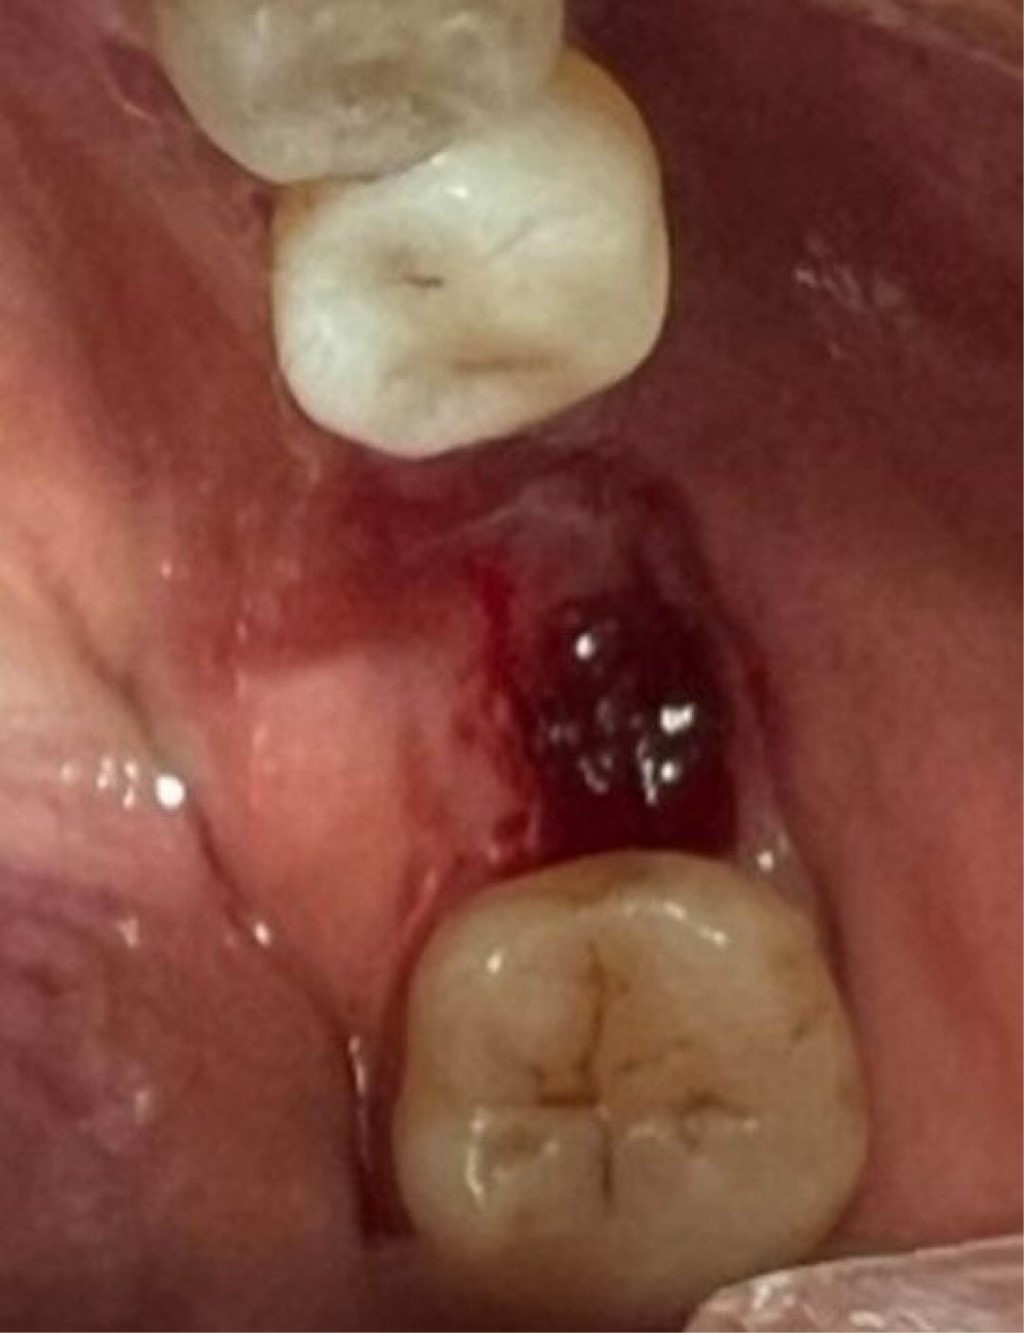

En mayo del 2024 el secuestro óseo se presentó como un fragmento móvil (Figura 3) y en las radiografías de control se evidenciaron signos sugerentes de aposición ósea por debajo del secuestro, por lo que, al presentarse asintomática la paciente, se decide realizar el retiro del secuestro óseo sin complicaciones, observando tejido blando bajo la zona correspondiente al secuestro óseo (Figuras 4 y 5).

Figura 3

Figura 4

Figura 5